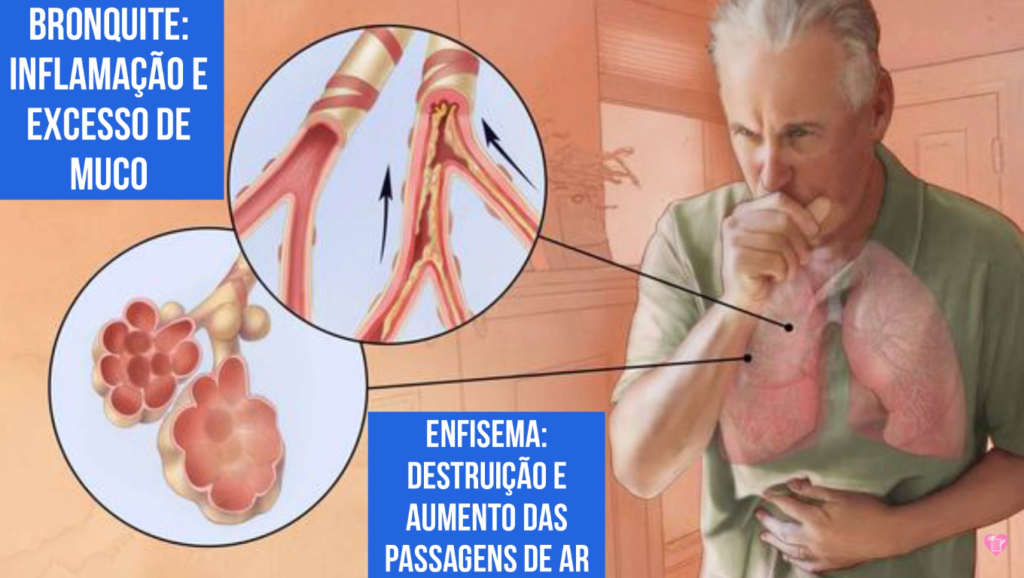

O enfisema pulmonar é a destruição do parênquima pulmonar, acarretando a perda da retração elástica dos septos alveolares e da tração radial das vias respiratórias, o que aumenta a tendência ao colapso destas. É sucedido por hiperinsuflação pulmonar, limitação do fluxo aéreo e aprisionamento de ar. Os espaços aéreos dilatam-se e com o tempo desenvolvem vesículas ou bolhas.

DPOC (doença pulmonar obstrutiva crônica) é um conjunto de doenças respiratórias, como bronquite crônica e enfisema pulmonar, que bloqueiam as vias aéreas e dificultam a respiração. A principal causa da DPOC é o tabagismo, pois a fumaça e outras substâncias presentes no cigarro prejudicam o tecido das vias respiratórias, levando ao.

A doença pulmonar obstrutiva crônica (DPOC) caracteriza-se pela limitação crônica ao fluxo aéreo, não totalmente reversível, associada a uma resposta inflamatória anormal à inalação de partículas ou gases nocivos.

Poluição do ar intra e extradomiciliar. Na DPOC, ocorre inflamação crônica das vias aéreas centrais e periféricas, parênquima e vasos pulmonares em resposta à inalação de partículas e gases nocivos, com acúmulo principalmente de macrófagos, neutrófilos e linfócitos T (sobretudo CD8).